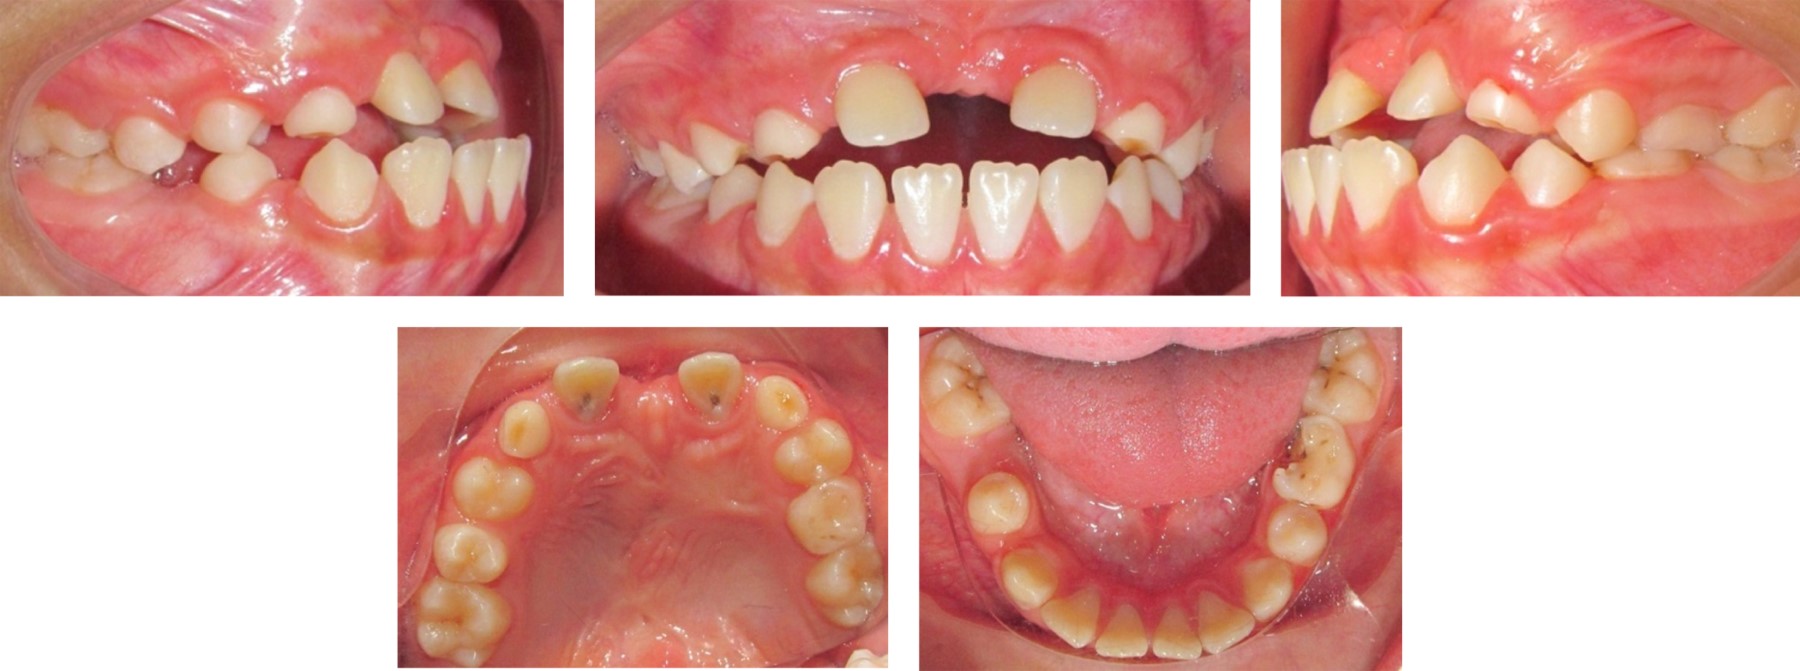

A 12-year-old male patient, with sequelae of secondary palate, presents at the Centro de Alta Especialidad "Dr. Rafael Lucio" with the consultation reason "my front teeth are missing", no allergies or habits; mesofacial biotype, oval face, symmetrical, mid-facial line with non-assessable teeth; dental organs #11 and #21 retained in horizontal position at apical level; openbite and anterior crossbite; bilateral class I molar; bilateral non-assessable canine class.

According to the extraoral and intraoral photographs (Figures 1 and 2), radiographic studies (Figures 3 and 4), and cephalometric data (Table 1), orthodontic treatment with traction of dental organs #11 and #21 was decided in order to fulfil the planned objectives. The treatment was carried out in three phases.

• Figure 1

Figure 2